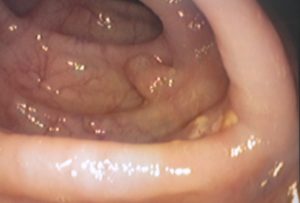

Внешне полипы в 12-перстной кишке имеют различные формы, такие как шаровидная, овальная или грибовидная. Поверхность полипов может быть бархатистой, гладкой, бугристой или зернистой. Ворсинчатые полипы напоминают цветную капусту. Опухоль имеет более темный цвет, чем слизистая оболочка, и насыщенность цвета зависит от структуры и количества сосудов с фибрином в ней.

Полипозные опухоли могут быть некрупными (до 20 мм), крупными (20-50 мм) или гигантскими (свыше 50 мм). Существуют различные типы полипов, такие как воспалительные, гиперпластические и неопластические. Неопластические полипы могут быть доброкачественными или злокачественными (аденоматозными), которые делятся на трубчатые, трубчато-ворсинчатые и ворсинчатые аденомы (подобные цветной капусте).

Фиброэзофагогастродуоденоскопия — это самый информативный метод диагностики, который используется для визуального осмотра слизистой оболочки пищевода, желудка и двенадцатиперстной кишки. Для этого используется специальный инструмент — эндоскоп, оснащенный камерой, оптикой и приспособлениями для взятия образцов тканей для гистологического, цитологического и морфологического анализа. Биопсия проводится с целью оценки структуры поврежденных тканей и определения характера полипа. Единственным противопоказанием для проведения биопсии является нарушение свертываемости крови. Если во время исследования обнаруживается полип, его можно сразу же удалить с помощью специальной металлической петли.